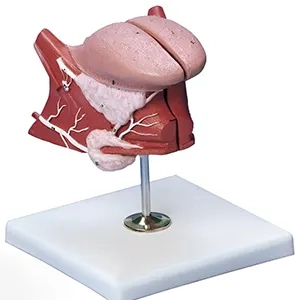

مولاژهای آناتومیکی: این دسته شامل مدلهای بدن کامل یا بخشهای خاص مانند قلب، ریهها، سیستم گوارش و غیره است. این مولاژها به درک بهتر ساختار و عملکرد اعضای بدن کمک میکنند.

مولاژهای فیزیولوژیکی: این مدلها به نمایش عملکردهای مختلف بدن مانند سیستم تنفسی، گردش خون، و دستگاه ادراری میپردازند.

مولاژهای پاتولوژیک: این مدلها تغییرات بیماریها و اختلالات مختلف را نمایش میدهند و به مطالعه و آموزش بیماریها و شرایط غیرطبیعی بدن کمک میکنند.

ماکتهای آناتومیکی: این ماکتها نمایانگر ساختارهای مختلف بدن انسان از جمله اسکلت، عضلات، سیستم عصبی و سیستمهای داخلی هستند. این ماکتها ممکن است به صورت کامل یا بخشهای خاصی از بدن مانند قلب، ریهها و کبد طراحی شوند.

ماکتهای فیزیولوژیکی: این ماکتها به نمایش عملکرد سیستمهای مختلف بدن میپردازند. برای مثال، ماکتهایی که نحوه کار سیستم تنفسی، گردش خون یا سیستم گوارش را نشان میدهند.

ماکتهای پاتولوژیک: این مدلها تغییرات بیماریها و اختلالات را شبیهسازی میکنند. آنها میتوانند به بررسی و آموزش بیماریهای مختلف، تومورها، عفونتها و آسیبها کمک کنند.

۱. مولاژهای آناتومیکی

- مولاژهای سیستمهای داخلی: مانند سیستم گردش خون، تنفسی و گوارشی، برای مطالعه و آموزش عملکرد این سیستمها.

۳. مولاژهای فیزیولوژیکی

این مولاژها برای درک و نمایش عملکردهای مختلف بدن طراحی شدهاند:

- مولاژهای قلب و عروق: برای آموزش عملکرد قلب و سیستم عروقی.

- مولاژهای ریه: برای مطالعه تنفس و ساختار ریهها.

- مولاژهای دستگاه گوارش: برای درک فرآیندهای گوارش و هضم غذا.